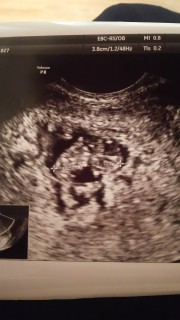

上が8w2d、下が8w3d、別の病院です。

前日は12.6mmで小さいのではないかと不安になっていたのですが、翌日の転院先では14mm以上あると言われてホッとしました。(1日しか違わないのに別の人のエコー写真みたい)

赤ちゃんの角度や測り方によっても変わると言われたので、正確ではないのと誤差も結構あるんだなと勉強になりました。

心臓もしっかり動いていて、「とっても元気」と言ってもらえました。

2cm程の筋腫が2つあるようですが、場所的に問題ないと言われました。